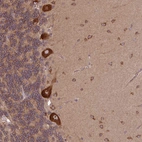

Immunohistochemical staining of human cerebellum shows strong cytoplasmic and nuclear positivity in Purkinje cells.